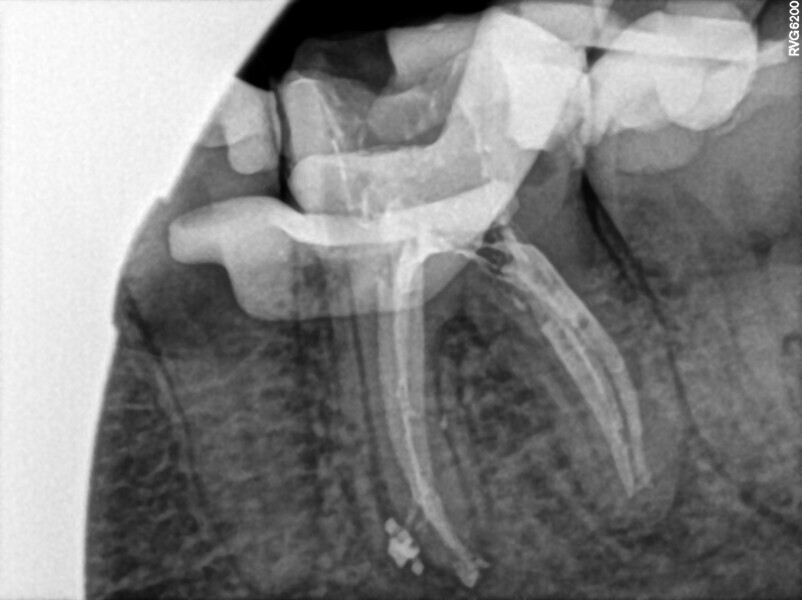

Post-op radiograph of a mandibular molar. (All Images: Bartłomiej Karaś)

A 25-year-old female patient presented to the office owing to constant pain related to the mandibular left first molar. Pulp necrosis was diagnosed. After the emergency appointment, the patient was referred for complete treatment. The tooth was treated in the same manner as described in the previous paragraphs. After creation of the access cavity, the orifices were located. In the root chamber, the orifices of the MB, mesiolingual, DB, distomesial and distolingual canals were present. After pre-flaring and preparation of the middle third, the LPE enhanced irrigation protocol with the SkyPulse laser was performed. After the irrigation protocol in the mesial root, the irrigants started to flow between lingual and buccal canals. Such an observation suggested to the operator that some space in the isthmus had been created. It is worth mentioning that at this stage apical enlargement was not performed. Final preparation of all five canals was performed with the reciprocating file, and the final irrigation protocol was performed as in the previous case. The radiograph clearly revealed that the isthmus space was filled with the sealer. The radiograph and CBCT image revealed that there were four portals of exit in the mesial root.